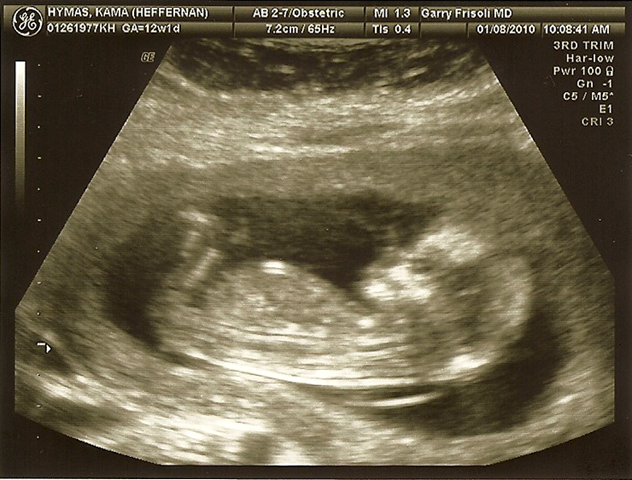

Good News

So there’s our big announcement-Let’s hope it’s a girl! And now I can post one of those cute baby countdowns on my blog! Needless to say this was by far the hardest Christmas of my life. It is NOT FUN to have morning sickness at Christmas time. Let me repeat for anyone who might be considering it. NOT FUN. All I can say is that it is a really good thing I got my Christmas shopping done in November this year or the boys would have gotten Happy Meal toys under the tree. But I will say here that I have the world’s most wonderful husband who picks up all the slack while I take my sick self and lie down. And he never ever complains. He is a saint and I love him very much.